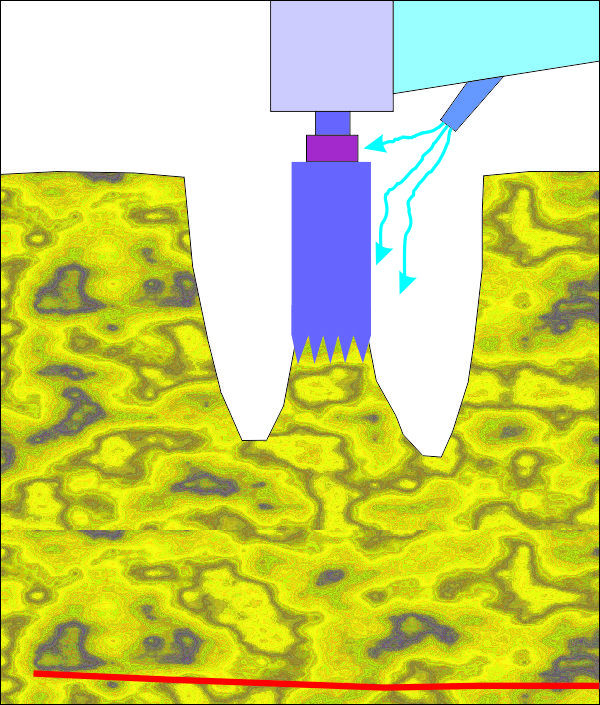

Пробиване с калиброващата фреза. Вижда се

водното охлаждане, което е важно за предпазване на костта от некроза вследствие

загряването